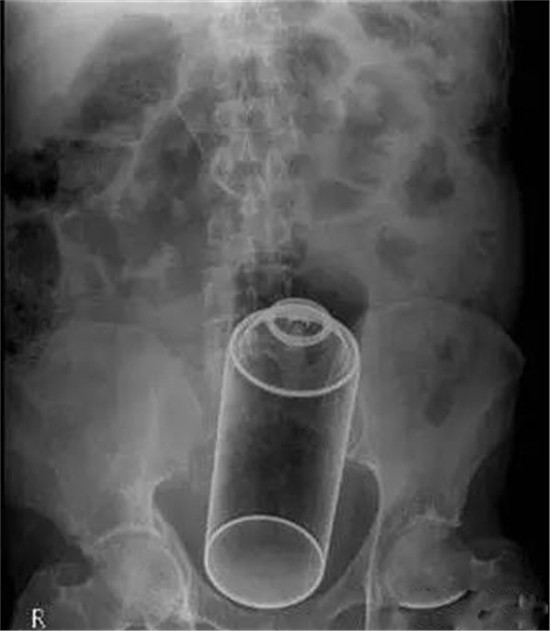

玻璃大瓶子

这是一个玻璃大瓶子。塞得相当深了,只有切开肚子取出来啦。